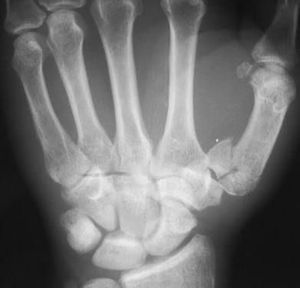

Identity the deformity and treatment

Fracture at base of first metacarpal

Correct! :) line of management for this fracture?

This case is of Bennett's fracture. It is fracture of base of first metacarpal. Usually it is treated with thumb spica and rest but in severe cases, k wires are used for adequate reduction.